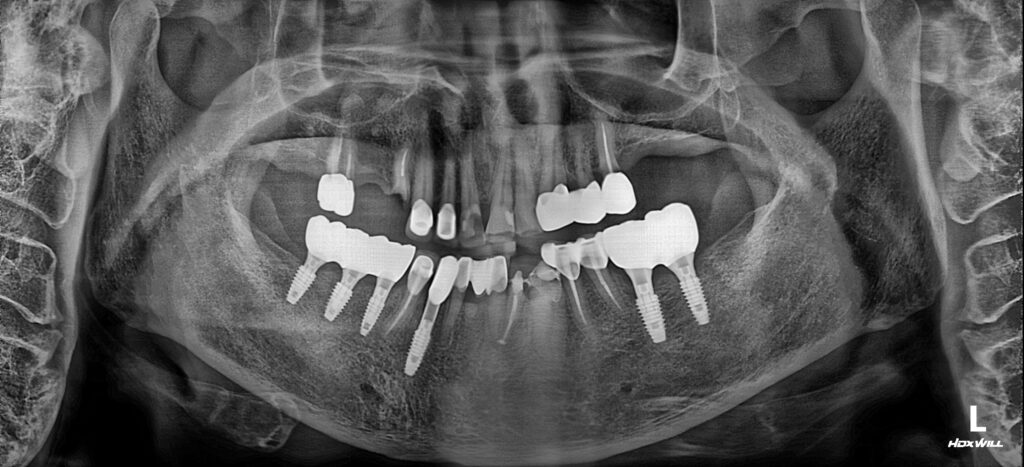

25.06.07

처음 내원하셨을 당시의 파노라마 방사선 촬영한 모습입니다. 치아상실과 뿌리만 남은 치아들, 치아우식, 치주질환으로 전반적으로 좋지못한 상태였습니다.

뿌리만 남은 치아의 상태가 매우 좋지 않아서 다시 살려서 사용하시기 어려운 상태였습니다. 영도치과 서울화이트S치과차근차근 아래 치아들 부터 진행하는 것으로 계획하고, 파절치는 발치 후 임플란트를 식립, 상실한 치아가 있던 자리도 임플란트를 식립하고 신경치료와 보존치료로 살릴 수 있는 치아는 살려사 사용하실 수 있도록 게획을 세워드렸습니다.